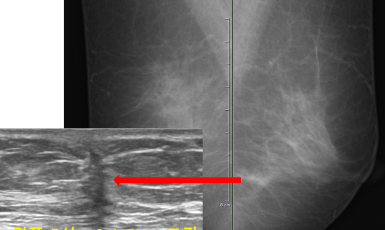

278번째 유방암 진단사례 (2020년1월21일) 왼쪽 유방에서 갑자기 만져진 멍울 증상으로 진료위해 내원한 환자분이셨습니다. 진찰상 왼쪽 유방의 위쪽에서 2cm 크기의..

작성자 레이디유 작성일 02-12 조회 15